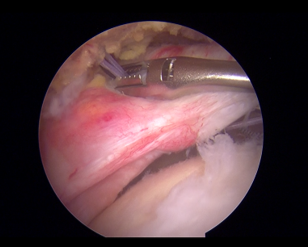

腱板断裂は、中高年に多く見られる肩関節疾患のひとつです。腱板断裂の原因は、加齢による変性と外傷が考えられます。50歳以降になると、腱板の変性が進み、腱板断裂が生じます。腱板断裂により上腕を挙上するときの痛みや、上腕を挙げにくいといった症状が出現します。腱板断裂の治療は、まず鎮痛薬や注射療法(ヒアルロン酸、ステロイド)などの保存治療を行います。しかし、3ヶ月以上の症状が続く場合は、腱板修復術の適応となります。当院では、鏡視下腱板修復術(Suture bridge法)を行っております。鏡視下腱板修復術は、1cm程度の小さな皮膚切開を5ヶ所加え、関節鏡下に専用のアンカーを用いて腱板を修復する低侵襲手術です。この手術により上腕挙上時の痛みを改善することが期待できます。

反復性肩関節脱臼は、初回の肩関節脱臼後に比較的小さな外力で肩関節が容易に脱臼する症状が特徴的です。原因は、前下方の関節唇損傷が考えられます。また、上腕骨頭と関節窩の損傷で関節窩前下方に骨欠損(骨性Bankart lesion)や、上腕骨頭の後外側の陥没(Hill-Sachs lesion)を認めることがあります。当院では、脱臼不安定感が持続する患者さんに対して、関節唇修復術(鏡視下Bankart法)を行っています。

肩関節周囲の組織に炎症が起きることが主な原因です。肩関節を包む袋(関節包、肩峰下滑液包)が癒着するとさらに動きが悪くなり、拘縮を生じます。注射療法やリハビリで治癒することが多いですが、肩関節の拘縮が続く患者さんに対しては、鏡視下関節包解離術を行っております。